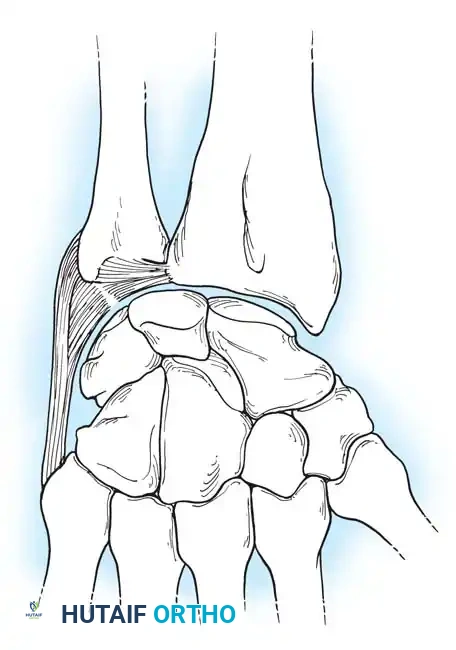

Capsuloligamentous Stabilizers

The stability of the carpus relies heavily on a complex network of intrinsic (interosseous) and extrinsic ligaments.

Palmar (Volar) Ligaments

The palmar ligaments are thicker and mechanically stronger than their dorsal counterparts. They are divided into extrinsic ligaments (connecting the forearm to the carpus) and intrinsic ligaments (connecting carpal bones to each other).

Key palmar extrinsic ligaments include:

* Radioscaphocapitate (RSC) Ligament: Acts as a sling supporting the scaphoid waist.

* Long Radiolunate (LRL) Ligament: Prevents ulnar translation of the lunate.

* Short Radiolunate (SRL) Ligament: Stabilizes the lunate to the lunate fossa.

* Radioscapholunate (RSL) Ligament (Ligament of Testut): Primarily a neurovascular conduit rather than a true mechanical stabilizer.

Clinical Pearl: The Space of Poirier is a distinct area of capsular weakness located on the palmar aspect of the midcarpal joint, between the RSC and the palmar radiolunotriquetral ligaments. It overlies the palmar surface of the lunate and is the classic site of capsular failure in perilunate dislocations.

Dorsal Ligaments

The dorsal capsuloligamentous network is thinner but biomechanically vital for preventing dorsal intercalated segment instability (DISI) and guiding carpal kinematics.

The Dorsal Radiocarpal (DRC) Ligament originates from the dorsal radial margin of the lunate fossa, spans the lunotriquetral joint, and inserts onto the dorsal triquetrum. Viegas and Mizuseki classified the DRC into four distinct morphological types based on its thickness and insertion footprint.

The Dorsal Intercarpal (DIC) Ligament originates from the dorsal triquetrum, courses transversely across the midcarpal joint, and inserts onto the dorsal scaphoid waist and trapezoid. Viegas verified three distinct types of DIC ligaments, noting that its laminated structure allows it to change shape dynamically during wrist motion.

Together, the DRC and DIC form a lateral "V" shape that stabilizes the proximal row and prevents dorsal subluxation during wrist flexion.